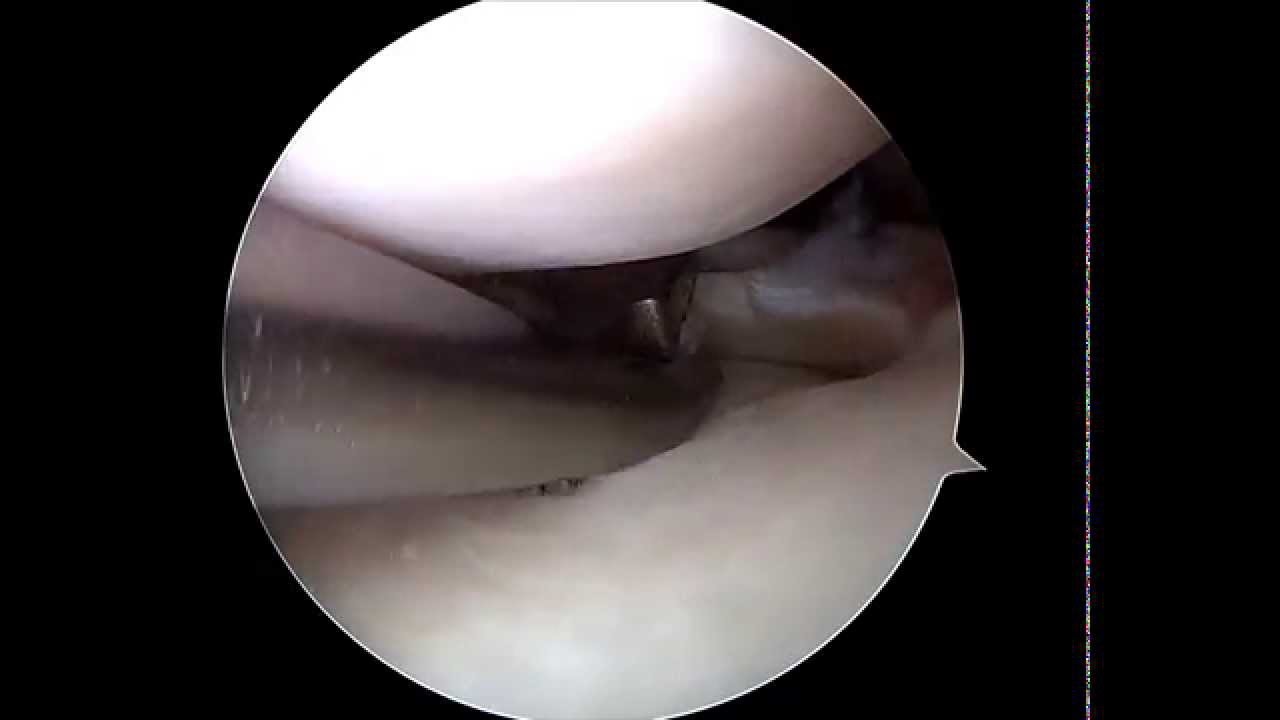

• Cirugía de menisco

Gran profesional!! Empatiza con el paciente; Se toma todo el tiempo necesario para explicar al detalle cualquier duda que se le plantee. Me inspiró mucha confianza desde el primer momento. Me operó del menisco interno y como nuevo!! Muchas gracias doctor!!

Muchísimas gracias por tus palabras y por la confianza que depositaste en mí desde el primer momento. Me alegra saber que te sentiste acompañado durante todo el proceso y que la intervención de menisco interno te ha permitido volver a encontrarte bien. Ese es siempre mi objetivo: explicar cada paso con claridad, tomar el tiempo necesario y ofrecer un tratamiento preciso y seguro para que cada paciente recupere su función lo antes posible.